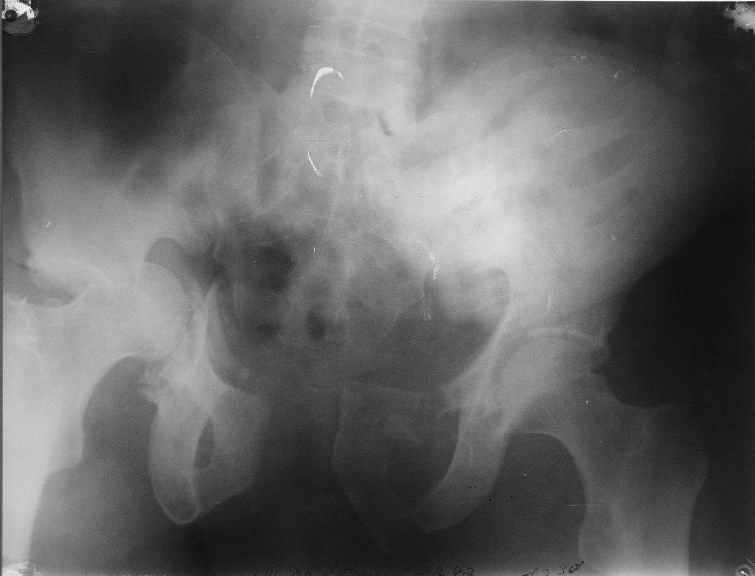

Уважаемый Антон, у Вашего больного имеется транстектальный поперечный перелом вертлужной впадины с переломом заднего края, перелом заднего типа, подвздошный вывих, возможна импрессия и повреждение нерва. Головка при этих повреждениях в нагружаемой части должна быть целой.

Доступ чрезвертельный, лучше Y образный, хотя при хорошем опыте можно и задне наружным (вертел придется отсекать).

Фиксация передней колонны трансфрактурным винтом, задней пластинами,мостовидной и упорной.

Разрыв лонного сочленения можно зафиксировать сразу после фиксации вертлуги из второго доступа.

Высылаю нечто подобное, аппарат пусть не смущает, просто больного оперировал через 2 месяца после травмы, а у него еще полный разрыв кп сочленения с контрлатеральной стороны.